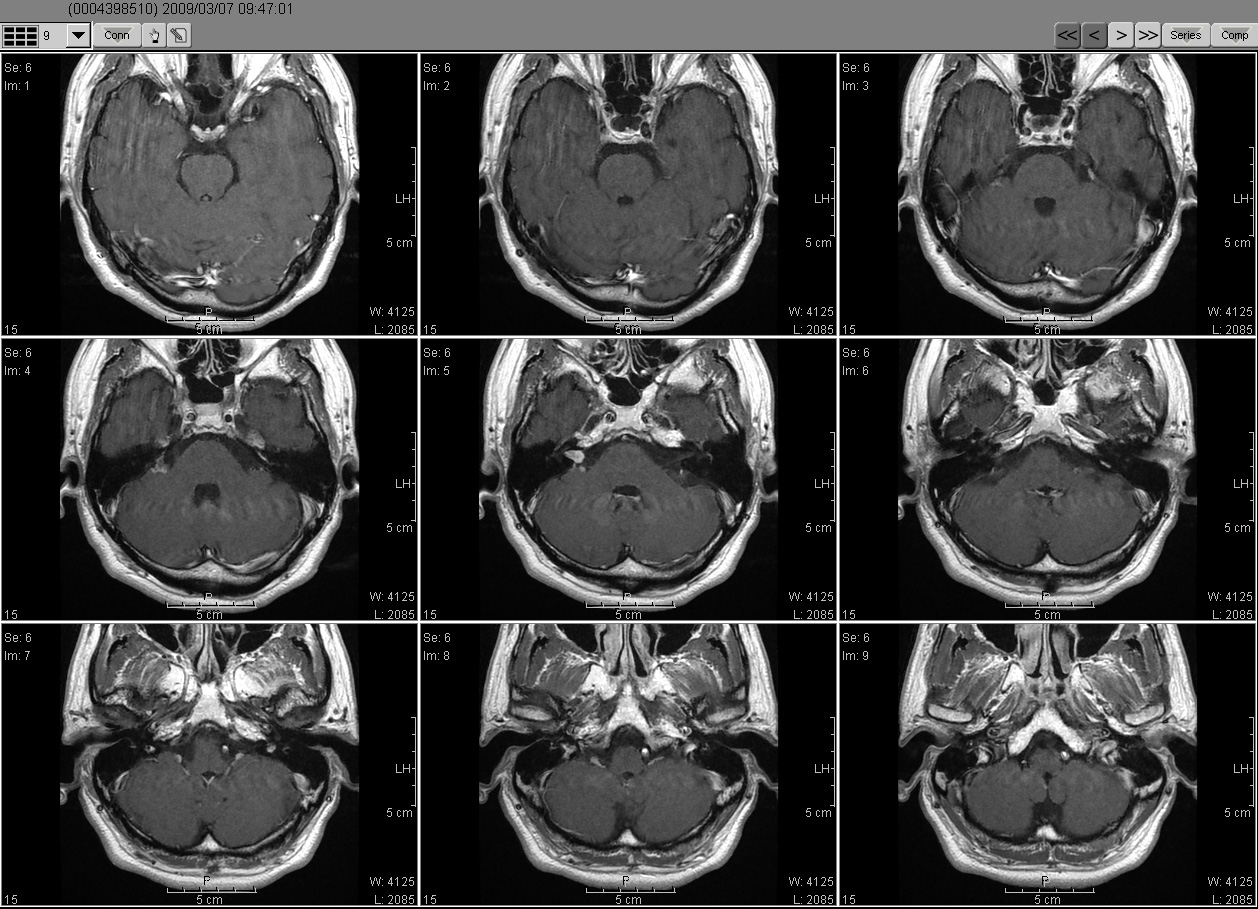

2009_03_07 MRI

2009_03_07MRI01